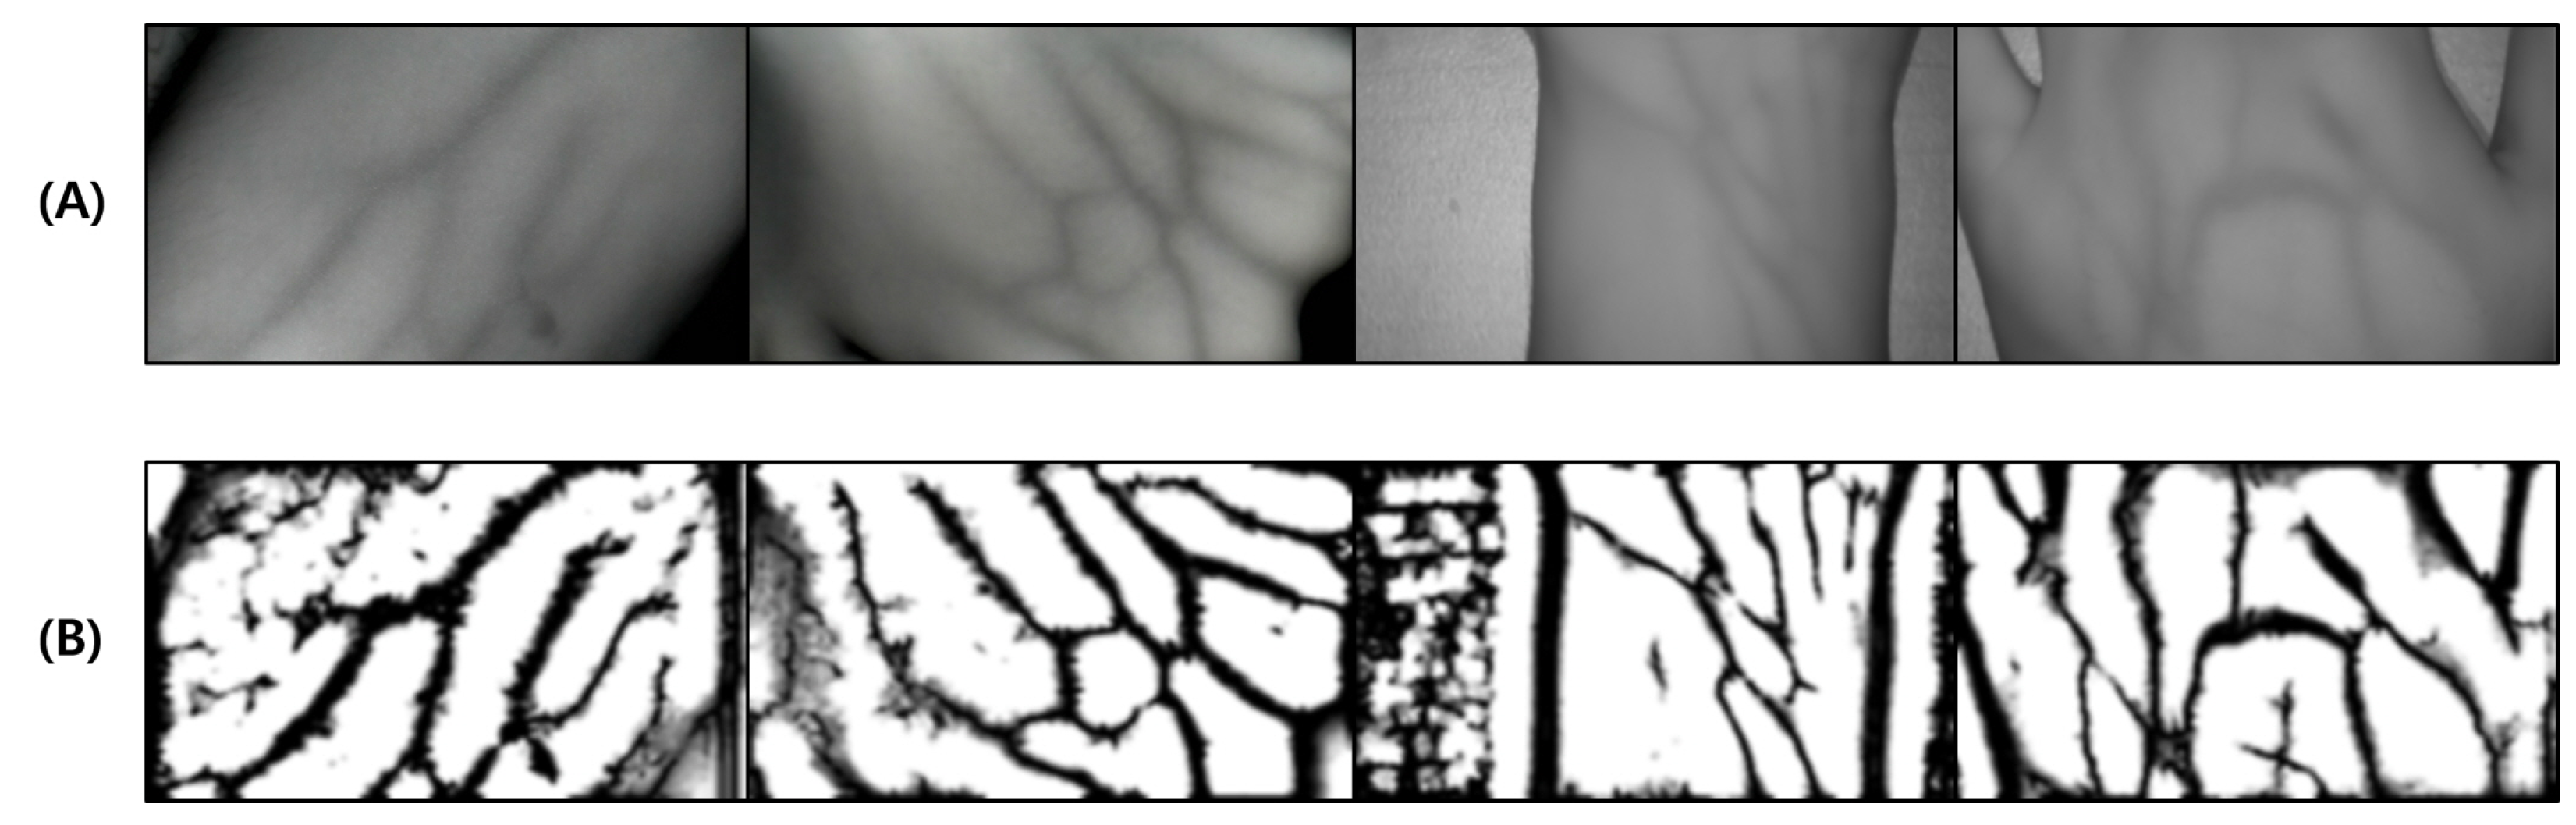

This test was conducted to verify the performance of the proposed vein image processing algorithm itself. Figure 18D was obtained based on the original image without body hair noise, and the performance of the proposed algorithm was verified with a total of 10 images.

Figure 18.

Image operation results without body hair noise: (A) is a test image created for algorithm verification, and (B) is an artificial blood vessel layer used to create the image. (C) is the resultant image of the proposed vein image processing algorithm, and (D) is the resultant image of the Veinvu-100 algorithm.

As a result of the test, in Figure 19C, output by the proposed algorithm, and in (D), output by the VeinVu-100 algorithm confirm the extent to which the path and thickness of the vein can be clearly identified. However, in the case of (C), the brightness of non-venous locations was significantly different from that of veins, and overall, noise was reduced. This makes it easy to grasp the length and thickness of the vein at a glance.

Figure 19.

Results of applying SSIM to the results of the proposed and Veinvu-100 algorithms: (A,B) are binary images of the results of applying the proposed and Veinvu-100 algorithms, respectively, and (C,D) are results of comparing (A,B) with the vessel layer using SSIM.

In the case of the original image (A), it can be seen that the histogram is relatively crowded due to the imbalance of lighting and weak contrast between each component. However, in the proposed algorithm (C), only vascular details with apparent differences were obtained by enhancing the visibility of blood vessels and removing noise components. Therefore, when confirmed with a histogram, it has a form similar to (B). In the case of (D), the contrast with the blood vessels was improved by weakening the vital noise component through image processing, and the blood vessels were captured generally because there was no body hair. However, the histogram has various contrast ratios due to noise detected from components other than blood vessels.

For objective performance verification between the proposed and Veinvu-100 algorithms, SSIM-based similarity evaluation was performed using the output images of each algorithm.

As a result of examining the similarity for all 10 images used in the test, the average similarity of the proposed algorithm was 86.52%, and that of the VeinVu-100 algorithm was 81.48%, indicating that the proposed algorithm improved performance by 5.04% compared to VeinVu-100. Detailed verification results can be seen in Figure 20 and Table 4 below.